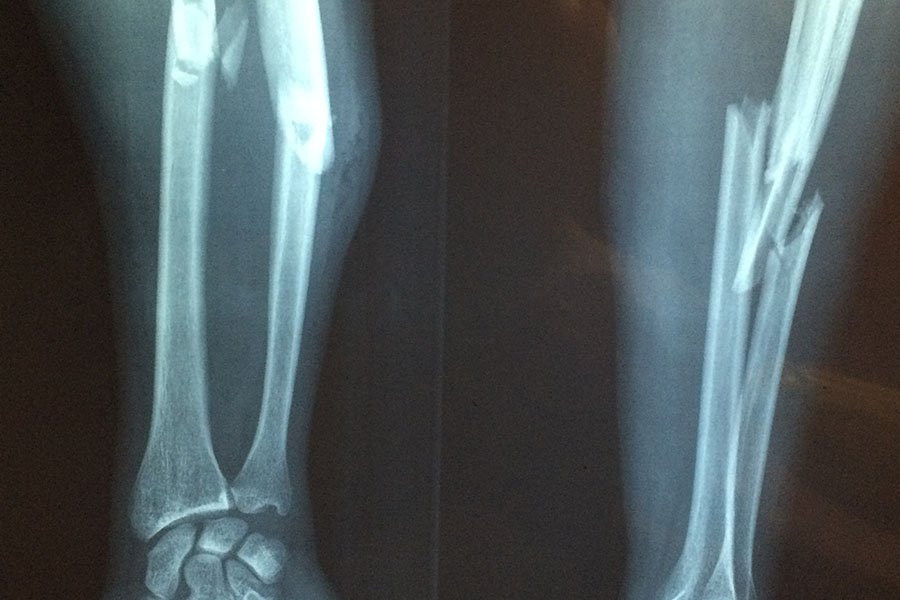

Фото из открытых источников

Переломы вследствие хрупкости костей, часто вызываемые остеопорозом (заболеванием, вызывающим хрупкость костей, склонных к переломам), поражают каждую вторую женщину и каждого четвертого мужчину, причем основным фактором риска является низкая минеральная плотность костной ткани (МПК).